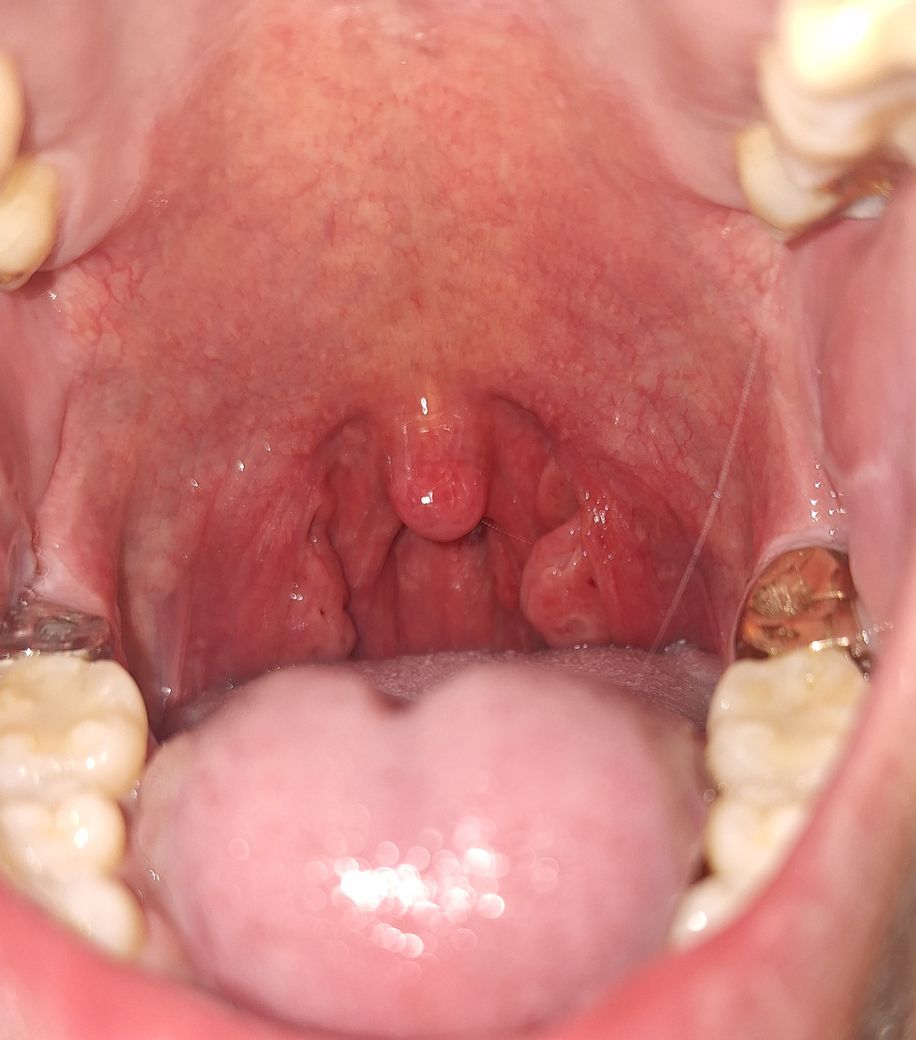

편도 상태 문의드립니다(수술여부)

어려서부터 편도결석이 자주 생기고 감기가 걸려도 목부터 안좋아진다는것은 알았지만 제 편도가 비정상이라고는 생각못하다가 최근에 인지했습니다ㅠ

혹시 수술을 요할정도로 편도가 커져있는 상태일까요? 아니면 가글 등 관리해준다면 괜찮을까요?

편도결석은 사진상 오른쪽에만 발생하고 왼쪽은 과거에는 생겼다가 최근몇년간 생긴적은 없습니다.

편도가 체질적으로 큰 편이시긴 합니다만 반드시 수술을 하여야 한다고 판단할 정도로 큰 정도라고 보기는 어렵습니다. 그렇지만 편도염이 빈번하게 발생하고 편도 결석이 반복하여 생기는 정도의 상태라면 수술적 치료를 고려해볼 수 있는 소견이긴 합니다.